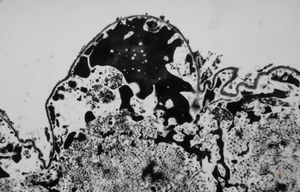

F,50y. | progressive multifocal leukoencephalopathy- viral particles in a glial cell